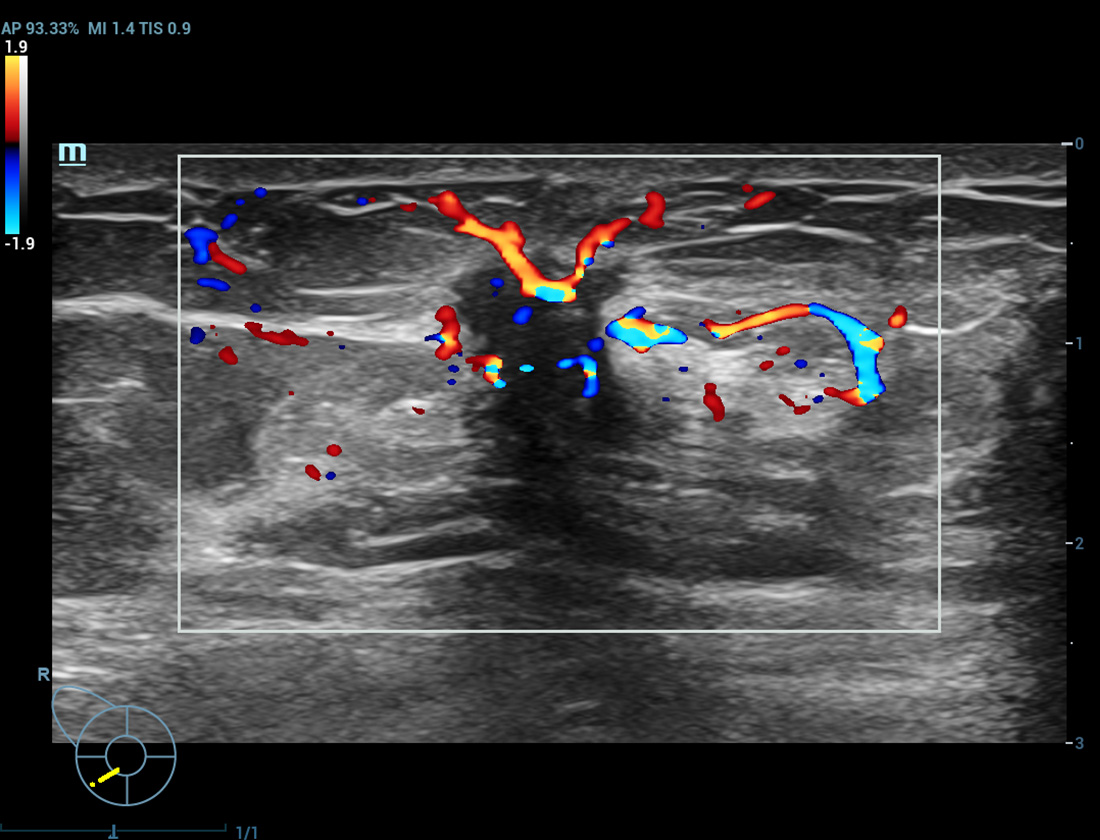

Ultra Micro Angiography (UMA)

UMA migliora la sicurezza diagnostica ampliando la visibilitĂ dei flussi sanguigni fino al livello dei vasi piĂč piccoli, con una sensibilitĂ e una risoluzione superiori.

Tumore alla tiroide sUMA